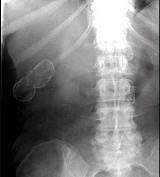

问题 女,39岁,右上腹部隐痛,有慢性胆囊炎史,曾经做过口服胆囊造影,胆囊未正常显影,X线检查如图,最可能的诊断是 ( )

选项 A.急性胆囊炎 B.慢性胆囊炎 C.胆囊结石 D.瓷样胆囊 E.胆囊结核

答案 D